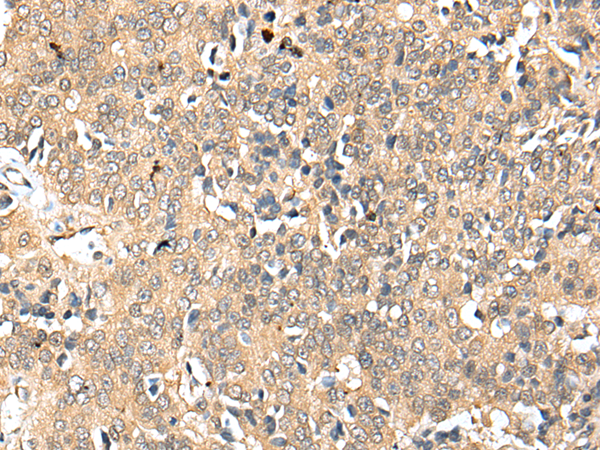

分类: 科研抗体货号: P09095别名: C8C应用: WB,IHC反应种属: Human